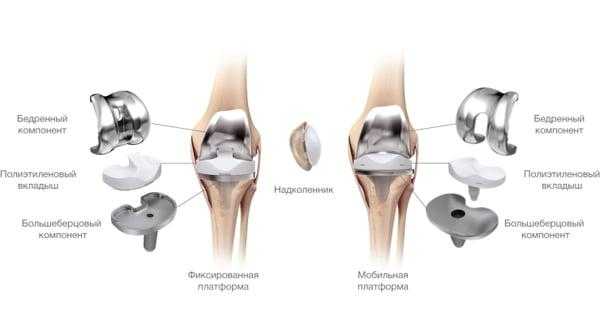

Множество различных видов протезов в настоящее время применяется при тотальном эндопротезировании коленного сустава. Почти все из них состоят из трех компонентов: бедренный компонент (сделан из хорошо отполированного прочного металла), большеберцовый компонент (состоит из крепкого полимера, часто расположенного на металлической платформе), и надколенника (также полимерный).

Макет импланта коленного сустава.